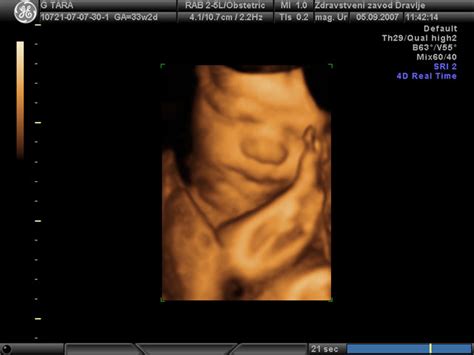

Z razvojem fetalne medicine v zadnjih desetletjih pa spremljamo tudi rast plodu že med nosečnostjo. Zastoj v rasti plodu se torej nanaša na ocenjeno velikost plodu, ki je manjša od pričakovane glede na trajanje nosečnosti. Ta ocena se izvaja z ultrazvokom (UZ), kjer se izmerjene vrednosti vnašajo v krivulje rasti za spremljanje razvoja.

V nekaterih primerih lahko pride do situacij, kjer ultrazvočne meritve kažejo odstopanja. Na primer, v enem od primerov je ginekolog ugotovil, da je plod manjši, z merami, ki so ustrezale 34. tednu (teža 2400g pri 38 tednih nosečnosti), pri čemer je bila glavica manjša, obseg trebuha pa normalen. V takšnih primerih, kot je pojasnil mag. Stanko Pušenjak, dr. med., specialist ginekolog in porodničar, to morda ni značilnost zastoja rasti, temveč podedovana manjša glavica. Obseg trebuha, ki ne kaže na pomanjkanje, je pomemben kazalnik.

Vsa ta pojasnila poudarjajo, da je interpretacija ultrazvočnih meritev kompleksna in zahteva strokovno znanje. Krivulje rasti so le povprečja, in velikost otroka lahko močno odstopa, ne da bi to pomenilo težavo. Ključno je, da ginekolog oceni, ali je z velikostjo otroka res kaj narobe, ob upoštevanju vseh dejavnikov.

Kako se z ultrazvokom izračuna teža ploda vašega otroka, katere meritve so potrebne?